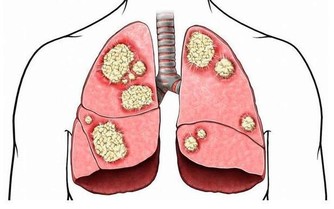

據統計,結腸癌早期患者的存活率大約是90%;但是如果忽視了身體發出的警告信號,

錯過了最佳的治療時期,當癌細胞擴散到身體其他部位時,治癒的希望會變得非常渺茫。